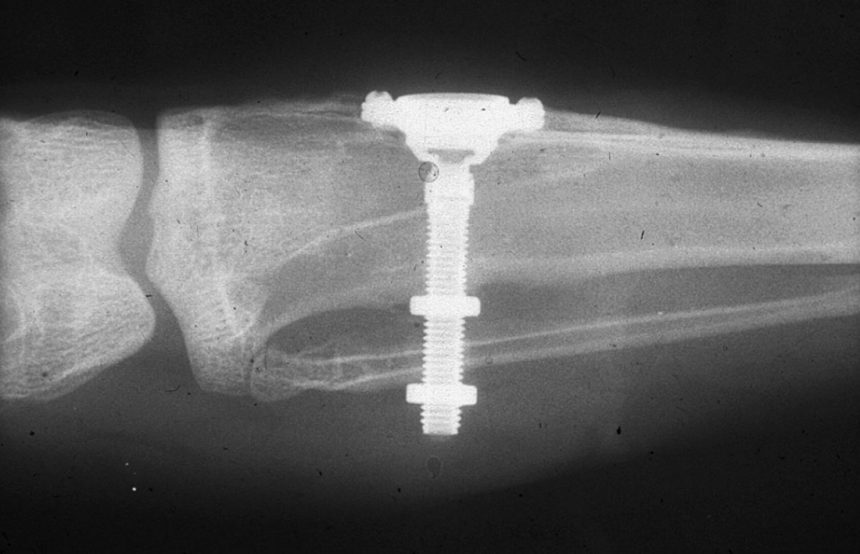

Рекомендации по установке имплантов. Для всех. Часть III